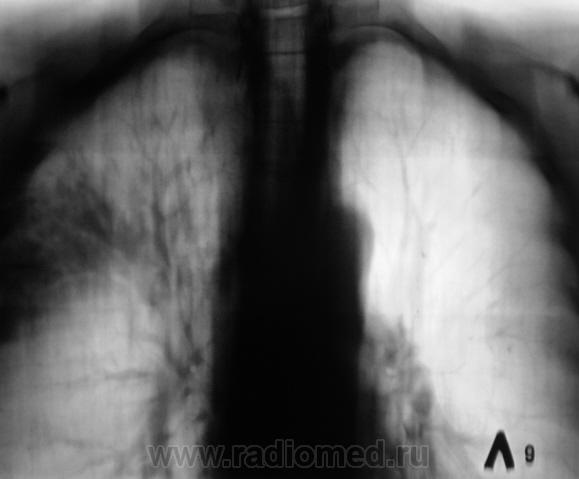

Произведена рентгенограмма в прямой стандартной проекции и томограммы в стандартных срезах.

«Пневмония», сразу показалась какой-то «фердиперсовой», с учетом лечения в стационаре ранее, довольно хорошего самочувствия пациента и наличием весьма «убогой» клиники. После проведения исследования было рекомендовано провести противовоспалительное лечение, исследование мокроты с целью проведения дифференциальной диагностики, рекомендована консультация фтизиатра.

Мы в протоколе, конечно, отметили, о возможности инфильтративного туберкулёза, д/д ряд даже не дали.

Но, мы стойко несмотря ни на что, стояли на тубере.

Пациент 4 месяца, по полной программе отлежал в областной конторе, ЦВК утвердило «инфильтративный». После выписки был направлен под надзор фтизиатра по месту жительства. Ниже иллюстрации после выписки.

Снимки сегодня.